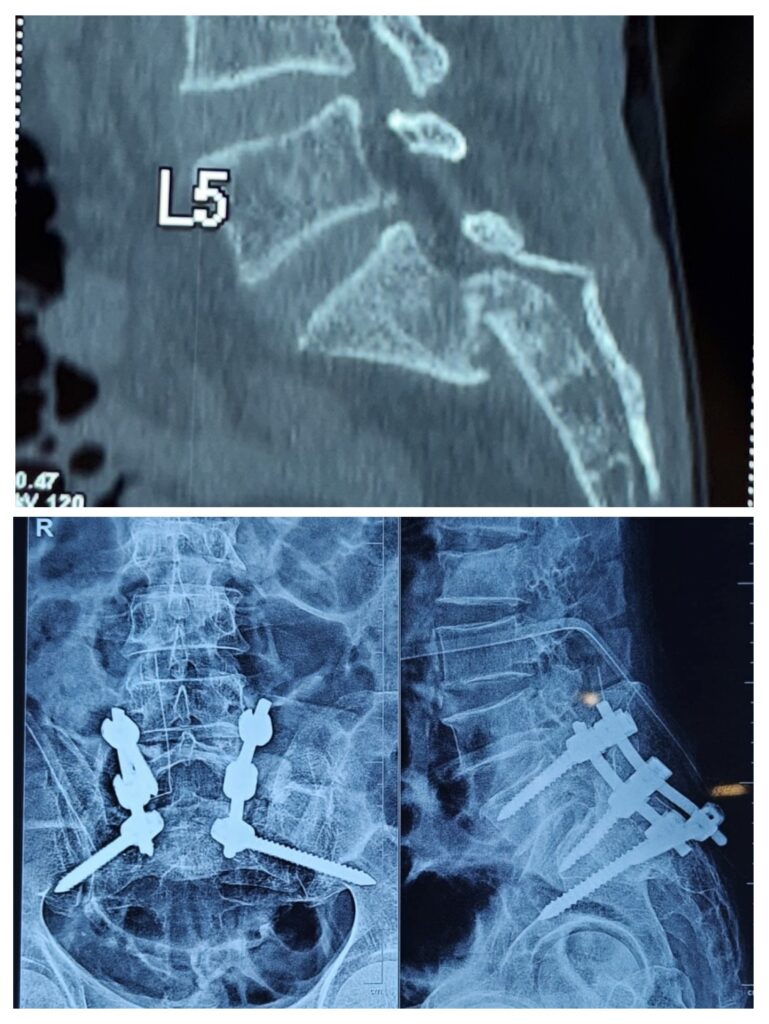

- X-ray: To detect fractures or bone alignment problems

- CT scan: Provides detailed images of the spine structure

3. Surgical Treatment (When Needed)

Common surgical procedures include:

- Spinal fixation: To stabilize fractured bones

- Decompression surgery: To relieve nerve pressure

Cases treated by Spine Specialist Dr. Gaurav Sandeep Gupta